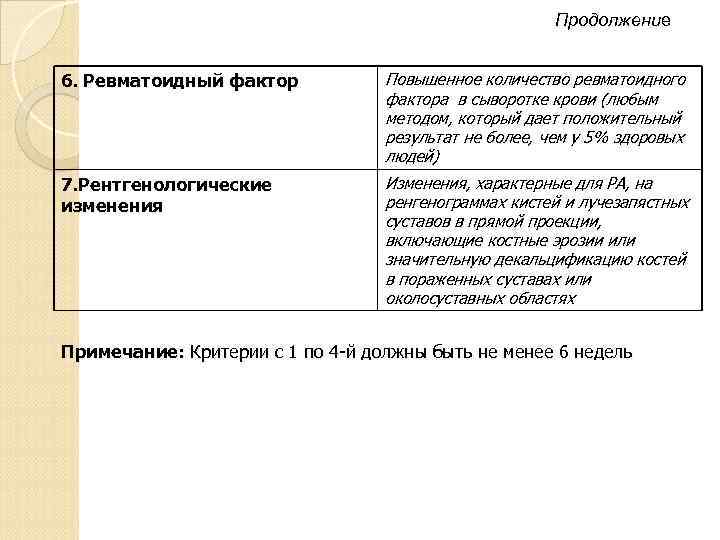

Продолжение 6. Ревматоидный фактор Повышенное количество ревматоидного фактора в сыворотке крови (любым методом, который дает положительный результат не более, чем у 5% здоровых людей) 7. Рентгенологические изменения Изменения, характерные для РА, на ренгенограммах кистей и лучезапястных суставов в прямой проекции, включающие костные эрозии или значительную декальцификацию костей в пораженных суставах или околосуставных областях Примечание: Критерии с 1 по 4 -й должны быть не менее 6 недель

Продолжение 6. Ревматоидный фактор Повышенное количество ревматоидного фактора в сыворотке крови (любым методом, который дает положительный результат не более, чем у 5% здоровых людей) 7. Рентгенологические изменения Изменения, характерные для РА, на ренгенограммах кистей и лучезапястных суставов в прямой проекции, включающие костные эрозии или значительную декальцификацию костей в пораженных суставах или околосуставных областях Примечание: Критерии с 1 по 4 -й должны быть не менее 6 недель